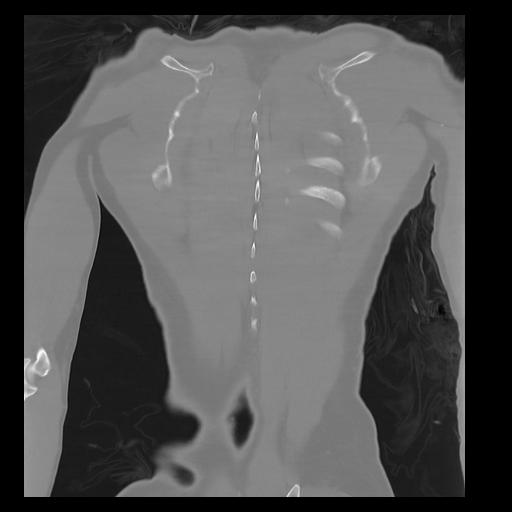

32 PULMON,CE,Coronal,3.000,PULMON,Coronal,